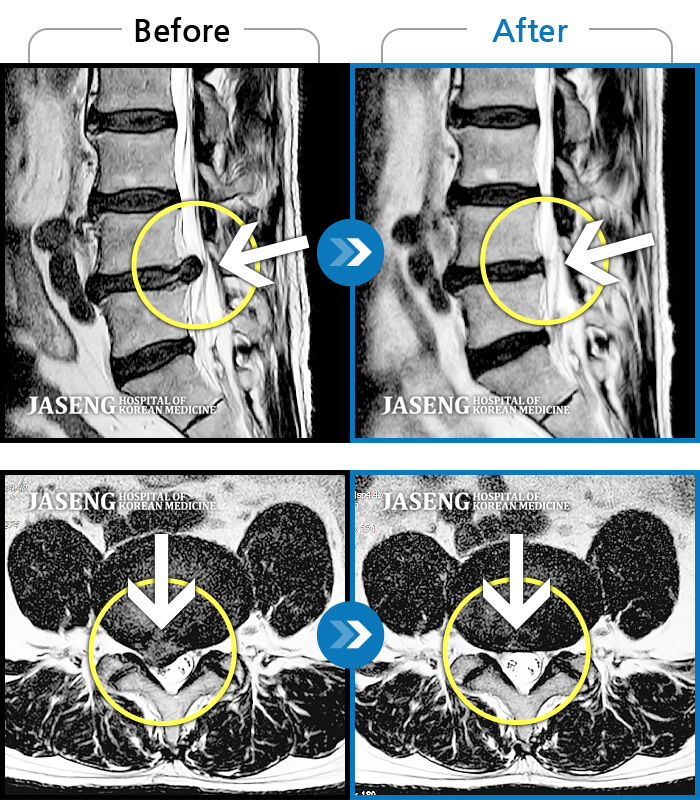

Before

After

허리 통증이 심하고, 양측다리 하지 쪽으로 땡기고 저려요.

2022.05.27 ~ 2022.10.28